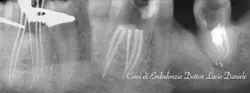

corso teorico-pratico in endodonzia chirurgica

Corso pratico endodonzia all'Aquila nel 2025L'AquilaVia Colle Pretara, 54, 67100 L'Aquila AQ, Italia -

corso teorico-pratico in endodonzia l'aquila: 17-18 gen, 31 gen-1 feb, 21-22 feb 2025

Corsi di endodonzia per odontoiatri e studentiL'AquilaVia Colle Pretara, 54, 67100 L'Aquila AQ, Italia -

corso teorico-pratico in endodonzia

Corso pratico su endodonzia a L'Aquila per odontoiatriL'AquilaVia Colle Pretara, 54, 67100 L'Aquila AQ, Italia -